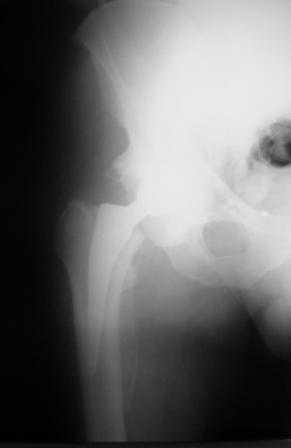

Больной Т. 56 лет, Диагноз: двухсторонний коксартроз 3-4 ст справа, 1-2 ст слева 2.10.08 выполнена операция тотальное бесцементное эндопротезирование. Использовался наружный доступ, положение на боку. Операция протекала без особенностей.

Выполнен послеоперационный ренгеноконтроль в прямой проекции. Рана зажила.

Уважаемый Глеб, предложенные снимки впечатлили! Никто не застрахован...